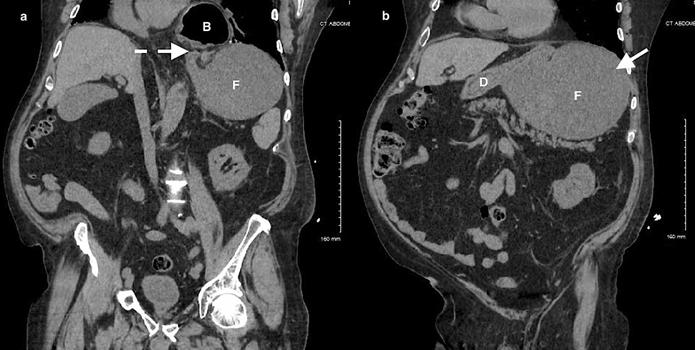

加急CT检查显示中至大型食管裂孔疝和由于胃扭转而显现的胃部水肿膨胀并伴有部分梗阻(图3-5)。

(图3)

(图4)

(图5)

当怀疑有胃扭转时,选择初始的影像学检查非常重要,因为诊断延迟可能导致致命的并发症。CT检查高度可靠,主要有两种表现,即正常的胃窦幽门移行区和胃窦位置异常,诊断急性胃扭转的敏感性和特异性均为100%。POCUS是一种有效的非侵入性影像检查方式,主要用于床旁评估。此外,POCUS无辐射,并可根据临床情况随时进行重复检查。本例患者POCUS检查显示,胃部严重扩张,胃内容物分层,类似胃出口梗阻(GOO)的“黑白饼干”征象。POCUS还可以用来动态视察胃减压成功与否。